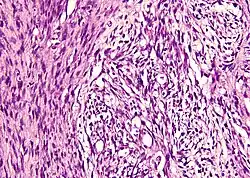

Złośliwy nowotwór osłonek nerwów obwodowych

Złośliwy nowotwór osłonek nerwów obwodowych (ang. malignant peripheral nerve sheath tumor, MPNST) – nowotwór złośliwy nerwów obwodowych, wywodzący się przypuszczalnie z komórek onerwia (perineurium). W około 50% przypadków występuje u pacjentów z nerwiakowłókniakowatością typu 1 (chorobą von Recklinghausena)[1]. Ryzyko rozwoju guza u pacjenta z NF1 w ciągu całego jego życia szacuje się na 7-12%[2]. MPNST jest guzem o dużej złośliwości (IV° według WHO).